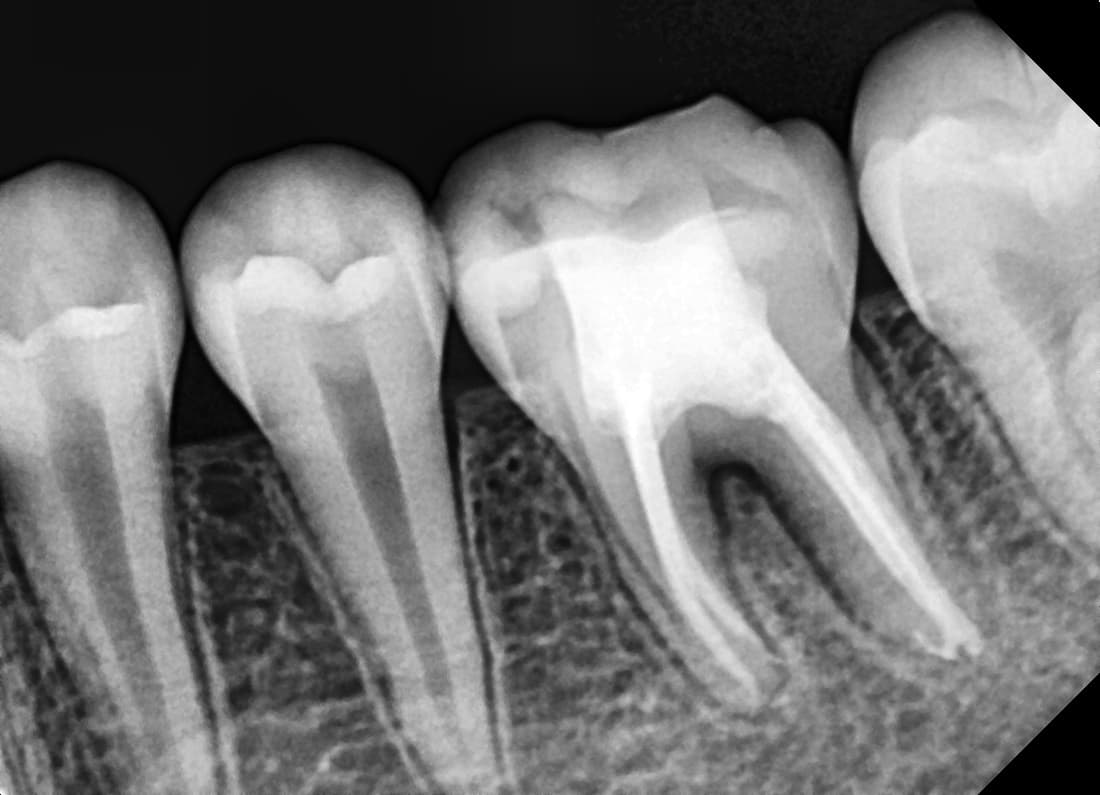

재신경치료

다른 병원 치료 후 재발한 어금니

Before

After

재신경치료로 추가 근관을 찾아 1년 9개월 후 완치